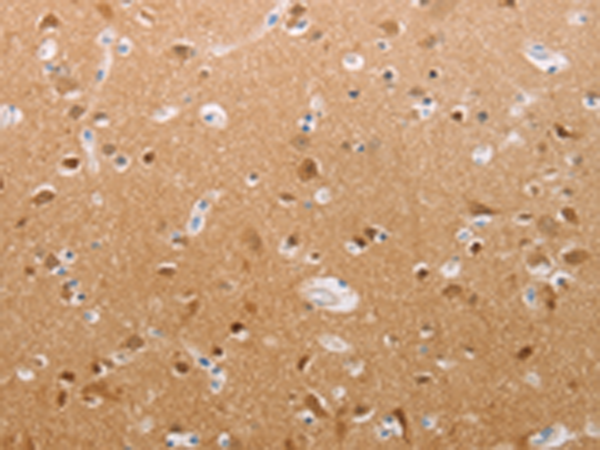

分类: 科研抗体货号: P04082别名: DBS, GP330应用: IHC反应种属: Human, Mouse, Rat